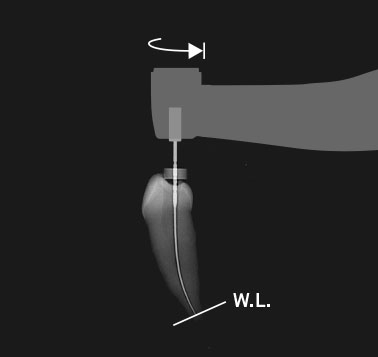

Il motore Tri Auto ZX2 è collegato alla funzione di misurazione del canale. Questa funzione rende il trattamento endodontico più sicuro ed efficiente. La posizione dell’estremità del file all’interno del canale viene visualizzata sul display ed il motore si arresta o avvia la rotazione inversa non appena il file raggiunge la fine della lunghezza di lavoro, al fine di evitare una strumentazione eccessiva.

Quando il file raggiunge la fine della lunghezza di lavoro, si inverte leggermente. Questo riduce la possibilità di rottura o inceppamento del file.